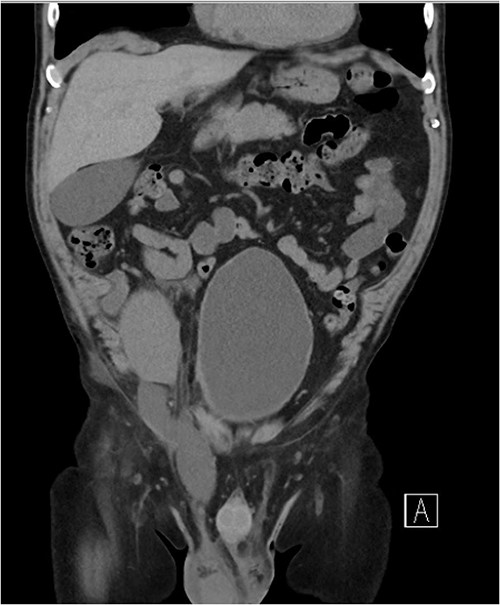

Three weeks postoperatively, the patient noticed a progressively enlarging right groin mass and associated discomfort. His examination was notable for a firm non-pulsatile non-reducible inguinal mass with no bowel sounds. He proceeded to have a CT Kidney, Ureter, Bladder (KUB), which revealed a small amount of perinephric collection (20 Hounsfield unit) marginating the posteromedial aspect of the transplant lower pole with a further fluid collection distending the right inguinal canal (10 Hounsfield unit) (see Fig. 1). The inguinal fluid pocket was localized with bedside ultrasound and 30 ml of clear fluid was aspirated with immediate symptom relief. The patient noticed reaccumulation of the fluid after a week and became symptomatic of pain again by the end of the third week.

Coronal CT image showing a dominant fluid collection extending off the lower pole of the transplant kidney into the right inguinal canal.